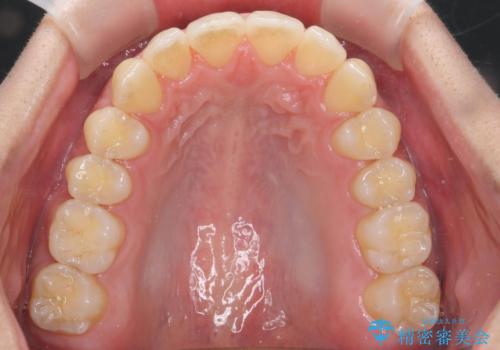

過蓋咬合・上顎前突・叢生を改善するマウスピース矯正

20時間以上のマウスピース装着、ゴムかけを遵守していただいたおかげでしっかりと噛み合わせ、がたつきの改善を行うことができました。